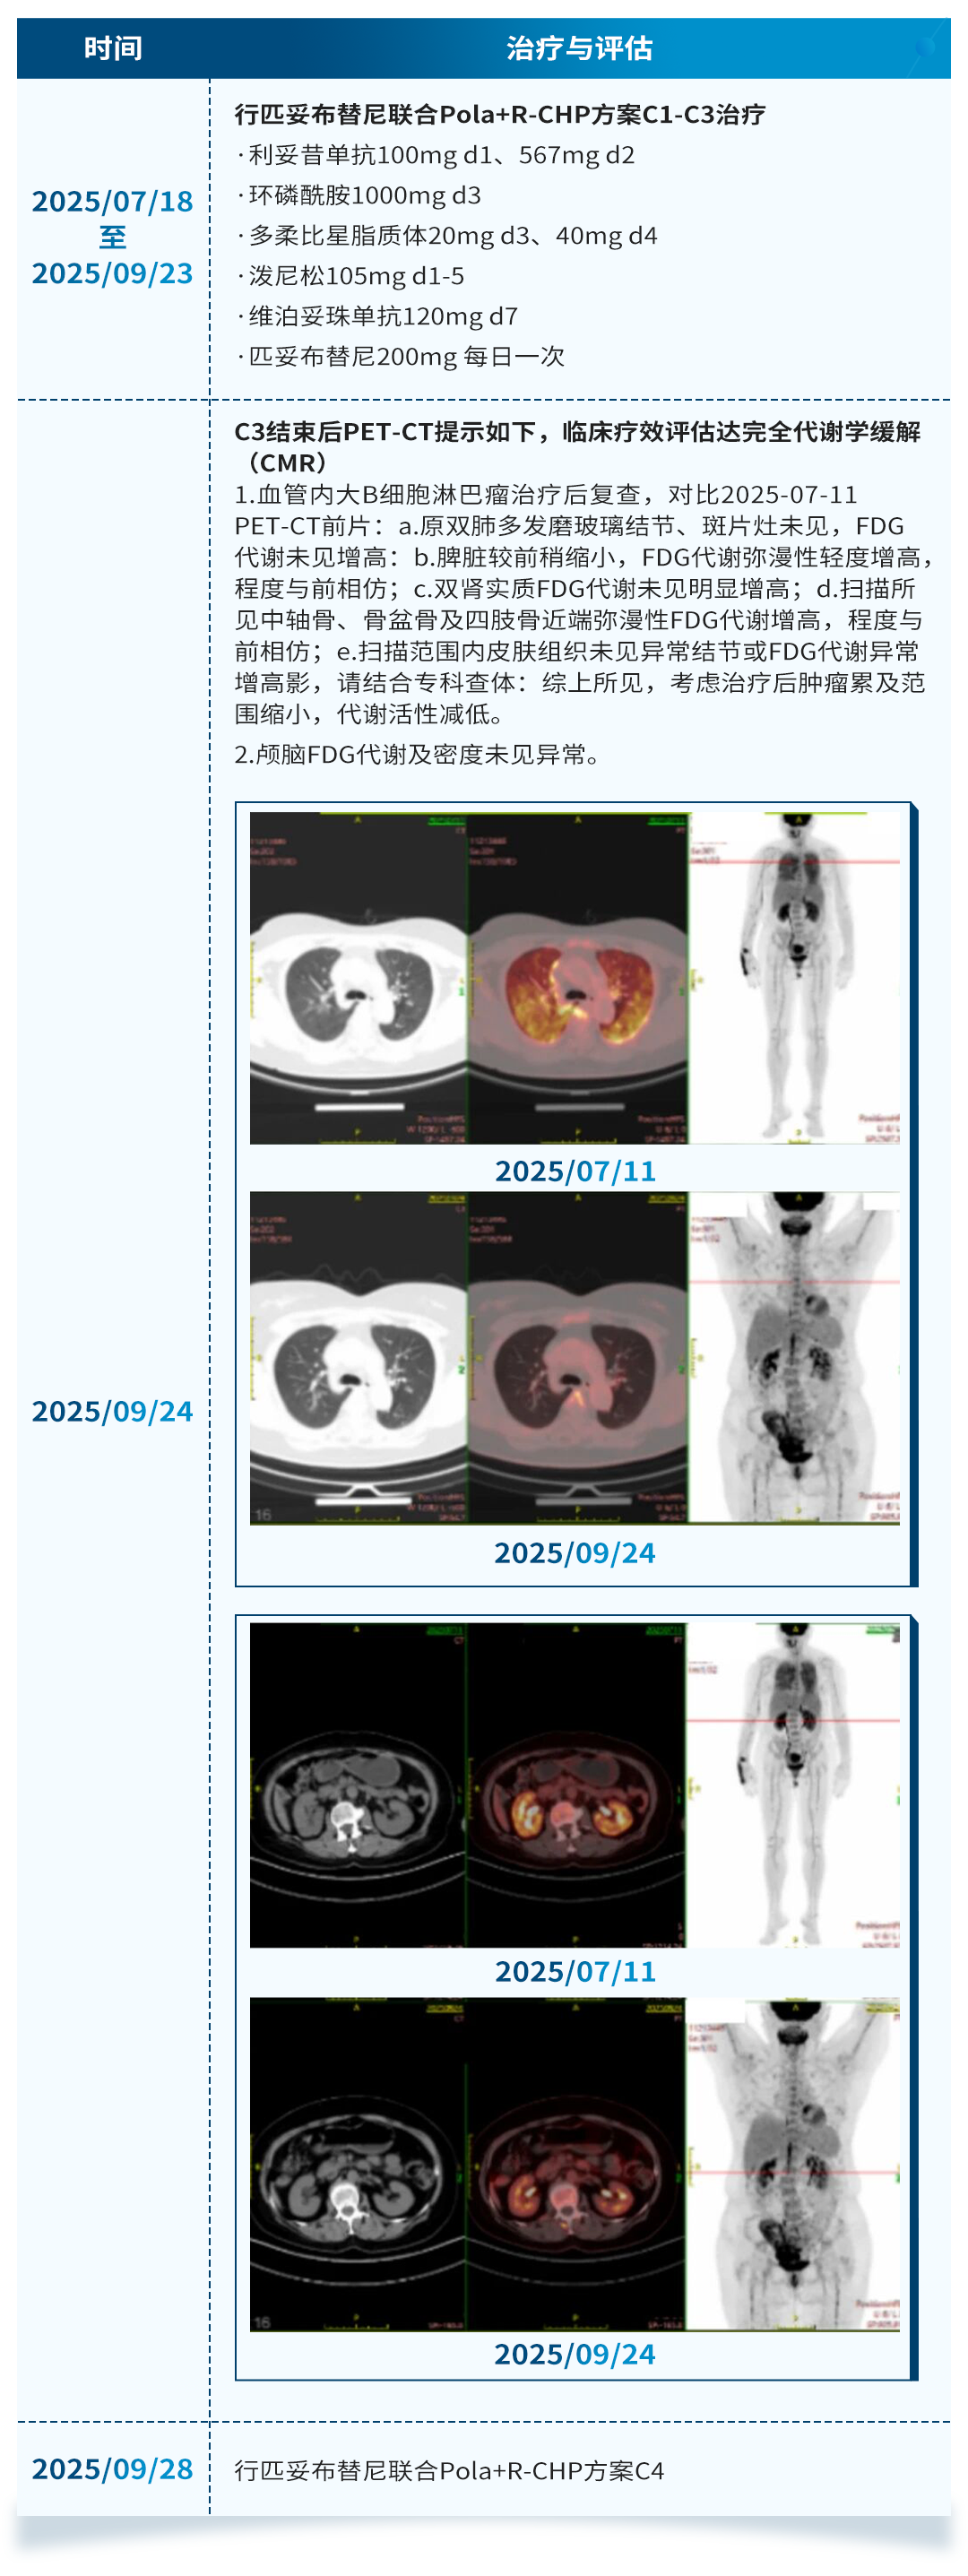

一线治疗

本次分享2例患者均为IVLBCL患者,其中1例为共价BTKi联合方案治疗后出现淋巴瘤颅内浸润无法继续行自体造血干细胞移植(ASCT)改用匹妥布替尼联合塞替派的治疗,2个周期治疗后获得了CR并成功进行ASCT;另一例为初诊患者,一线治疗直接选择匹妥布替尼联合Pola+R-CHP,3个周期治疗后获得了CMR,后续会考虑序贯ASCT。这两个病例提示匹妥布替尼联合治疗方案在IVLBCL患者中具有良好的疗效与安全性。未来还需更更大规模的人群以及随机对照研究来证实匹妥布替尼联合方案在IVLBCL患者中的疗效与安全性,以改善此类患者的生存结局。此外,IVLBCL患者复发后的生存极差,如何避免或延缓复发是临床关注的另一问题。缓解后序贯ASCT巩固治疗的IVLBCL患者的3年PFS率和OS率分别为83%和89%,3年累积复发率为14%[7][8]。因此,本次分享的两个病例均考虑在治疗缓解后进行ASCT。